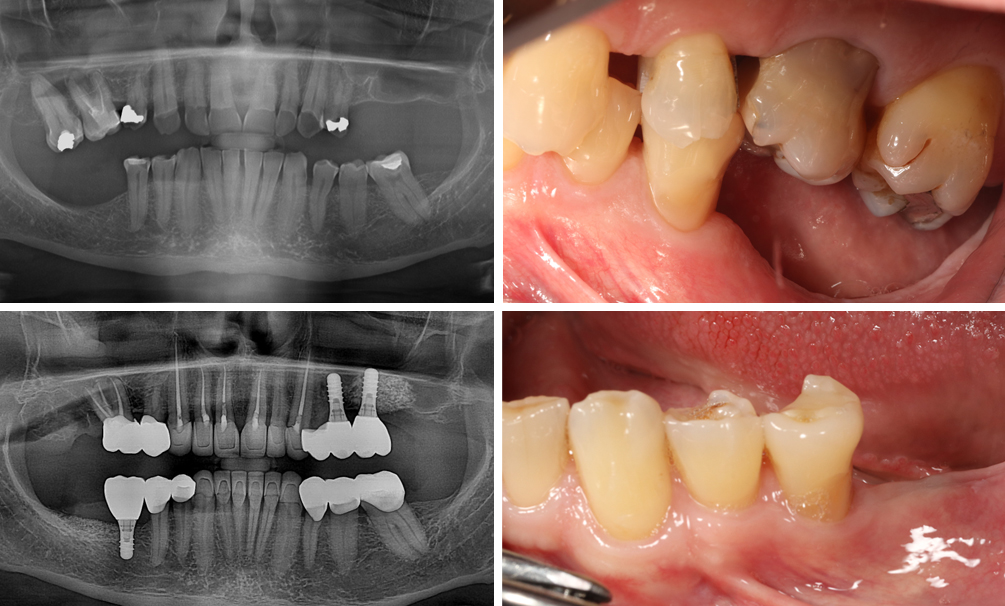

Teljes szájrehabilitáció

Nem minden száj alkalmas arra, hogy koronát vagy héjakat készítsünk.

Ezekben az esetekben egy teljes komplex ellátásra van szükség, aminek több lépésből áll: harapás állítás, backward planning és teljes száj rehabilitáció, korona, betét, héj készítése esettől függően…